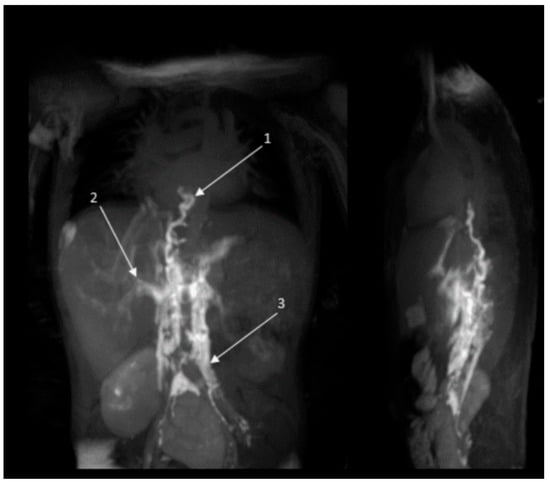

2.2.2. Radiology Assessment Before and After Treatment